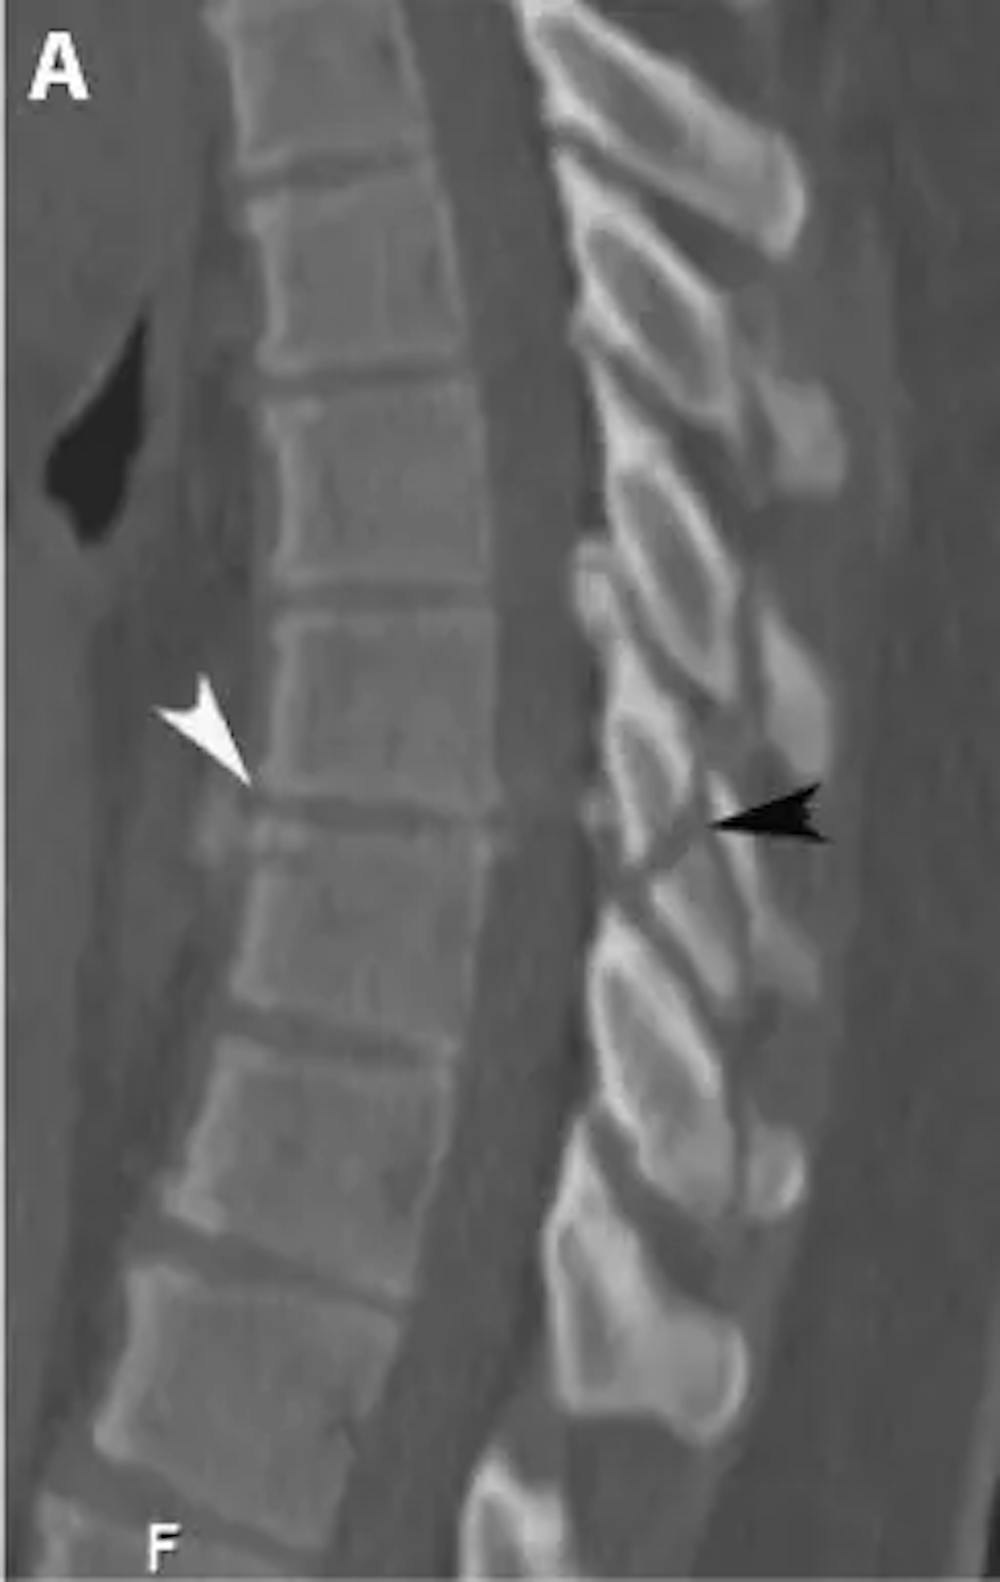

A) پری آپریٹو سیگیٹل سی ٹی اسکین چھاتی کی ریڑھ کی ہڈی کے فریکچر کی نقل مکانی کو ظاہر کرتا ہے۔ ڈسک کی جگہ میں خلل پڑتا ہے (سفید تیر کا نشان) اور پہلو کے جوڑ ٹوٹ گئے ہیں (سیاہ تیر کا نشان)۔